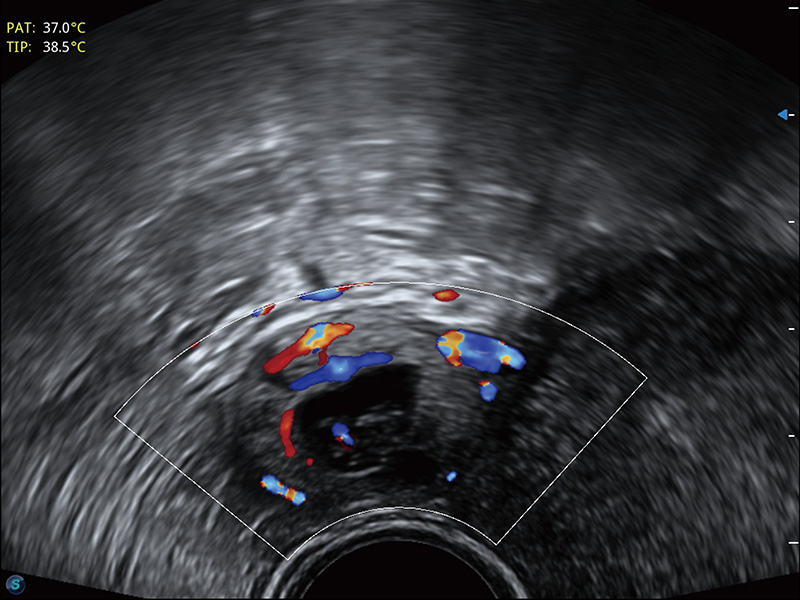

“生育问题”即关系民族复兴,也关系亿万家庭的幸福。随着婚育年龄推迟、社会压力增加等因素,越来越多人群也面临着“生不出、生不好”的问题。辅助生殖作为治疗不孕不育最有效的方法之一,也逐渐成为育儿新希望。而超声检查能为生殖需求人群的初诊评估提供宝贵的信息。 P20 Elite是新葡的京集团8814检测站匠心打造的一款生殖应用型彩超。她继承新葡的京集团8814检测站高端极光平台,突破性地将多款新型芯片及硬件模块进行整合,均衡了高端系统性能与小巧灵动机身。P20 Elite卓越的图像质量搭载专科探头,旨在为您提供全面的辅助生殖解决方案。

P20 Elite配备了丰富的生殖探头群和临床应用功能,在卵泡监测、穿刺取卵、胚胎移植、妊娠确认等领域,为生殖需求人群提供了新的临床机会,重新定义高端超声如何应用于生殖健康检查。

耦合剂加热器可将耦合剂维持在舒适的温度,体现患者关爱。